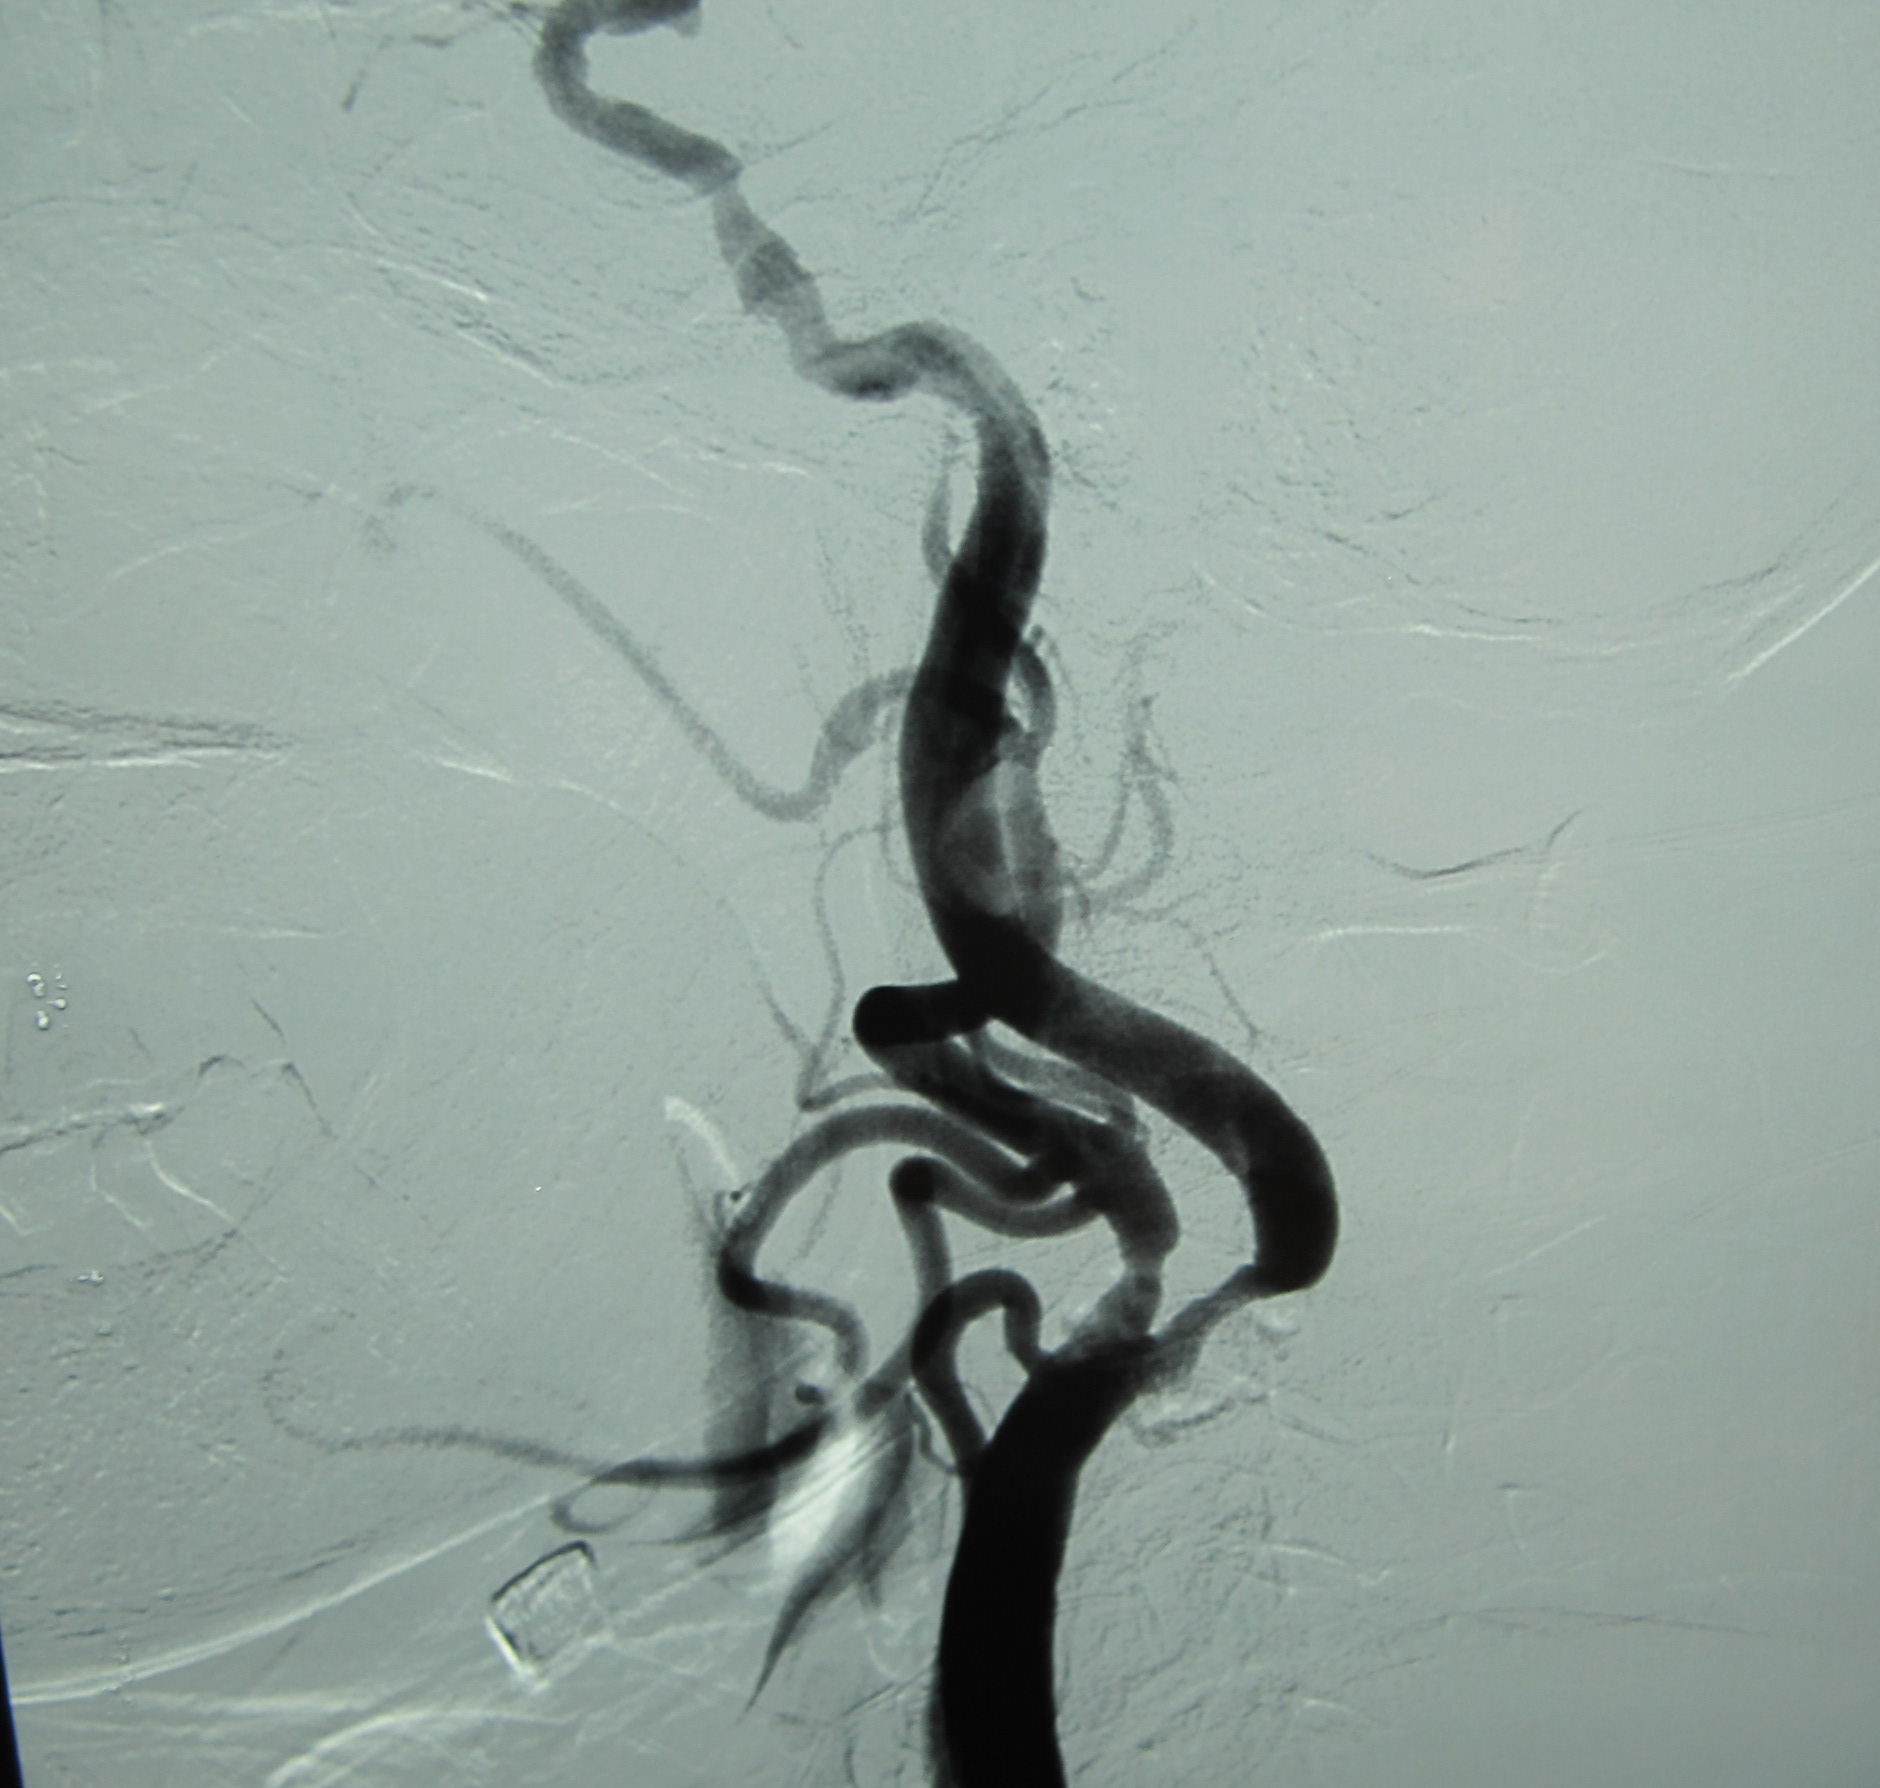

DSA:双颈内动脉起始端、虹吸段、左颈外动脉起始段多发动脉粥样硬化性改变伴狭窄。

患者老年女性,因发现双侧颈动脉狭窄4个月入院。DSA:双颈内动脉起始端、虹吸段、左颈外动脉起始段多发动脉粥样硬化性改变伴狭窄。手术指征明确。2011年11月10日张勤奕教授为其施行了颈动脉剥脱术,术后恢复良好,顺利出院。